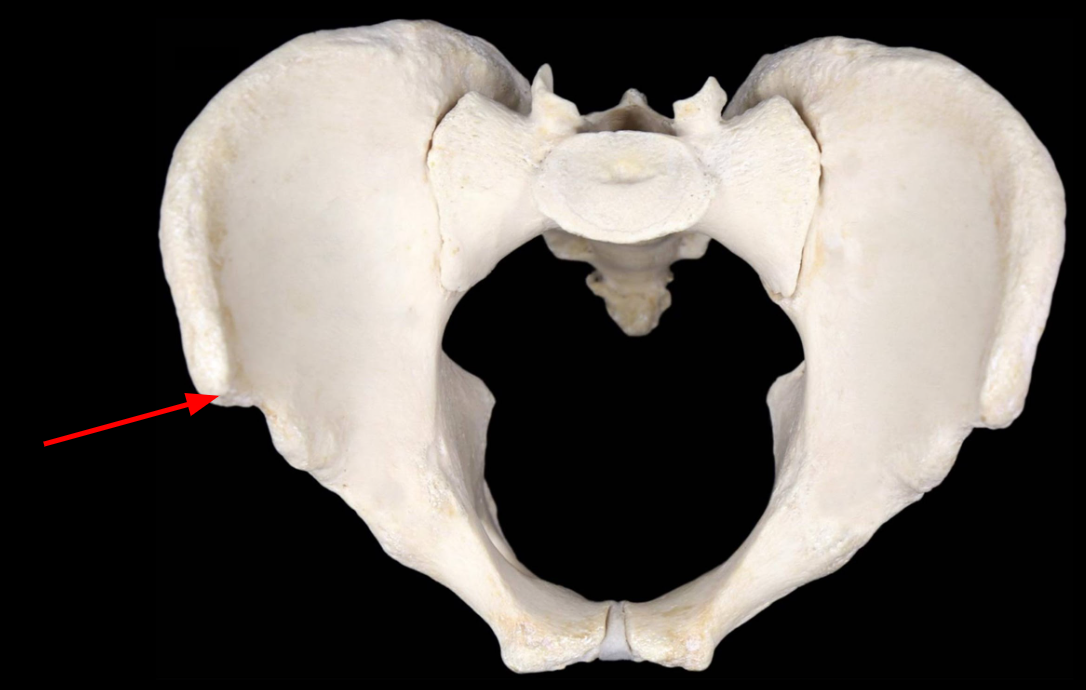

Greater Sciatic Notch